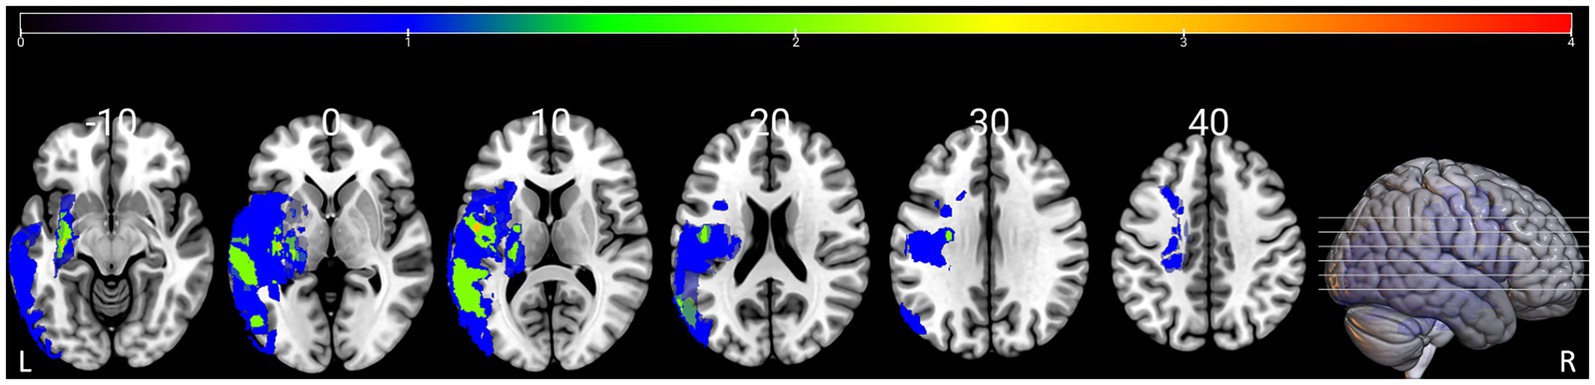

There were no significant inter-group differences in terms of age, sex or education level (all p > 0.05). Table 1 shows the demographic information, language assessment scores of the participants. The lesion overlap map for all patients with PSA is presented in Figure 1.

Figure 1. Lesion overlap map for the 12 patients with PSA in MNI space. Color bar represents the number of patients with overlapping lesions at certain locations. The numbers refer to the MNI coordinate space in the z plane. L = left, R = right.